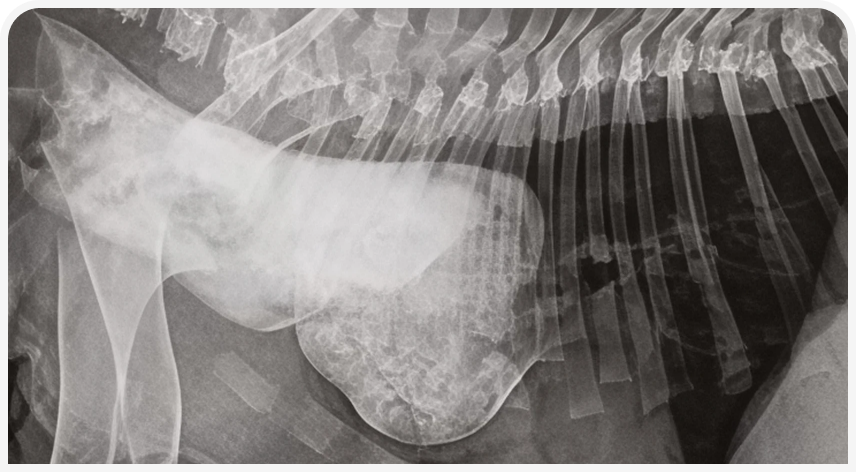

Врожденные аномалии развития. Статья из книги «Неонатология и педиатрия собак и кошек»

«Врожденные аномалии развития »!